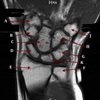

A

SUBSCAPULARIS MUSCLE

How well did you know this?

1

Not at all

2

3

4

5

Perfectly